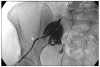

Figures